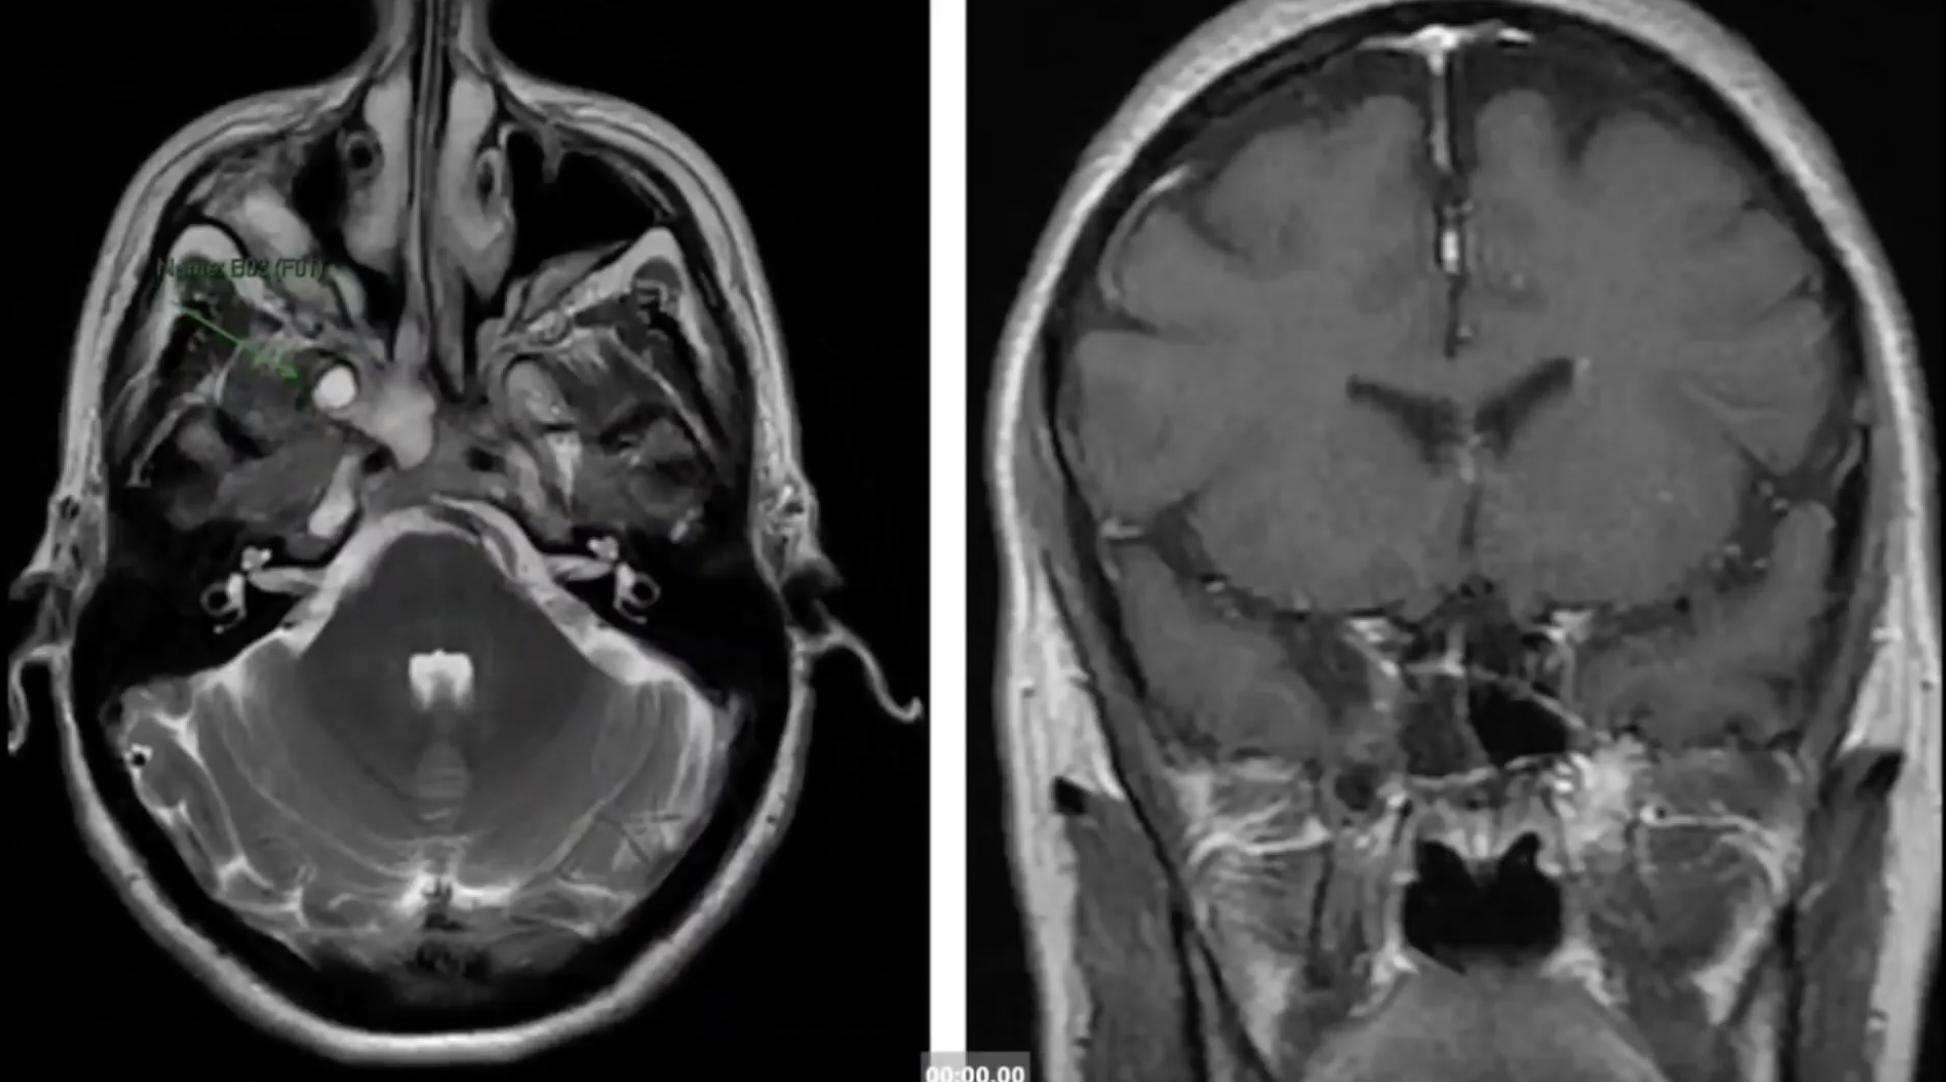

A way to improve skull base surgery through the advanced application of endoscopic techniques.